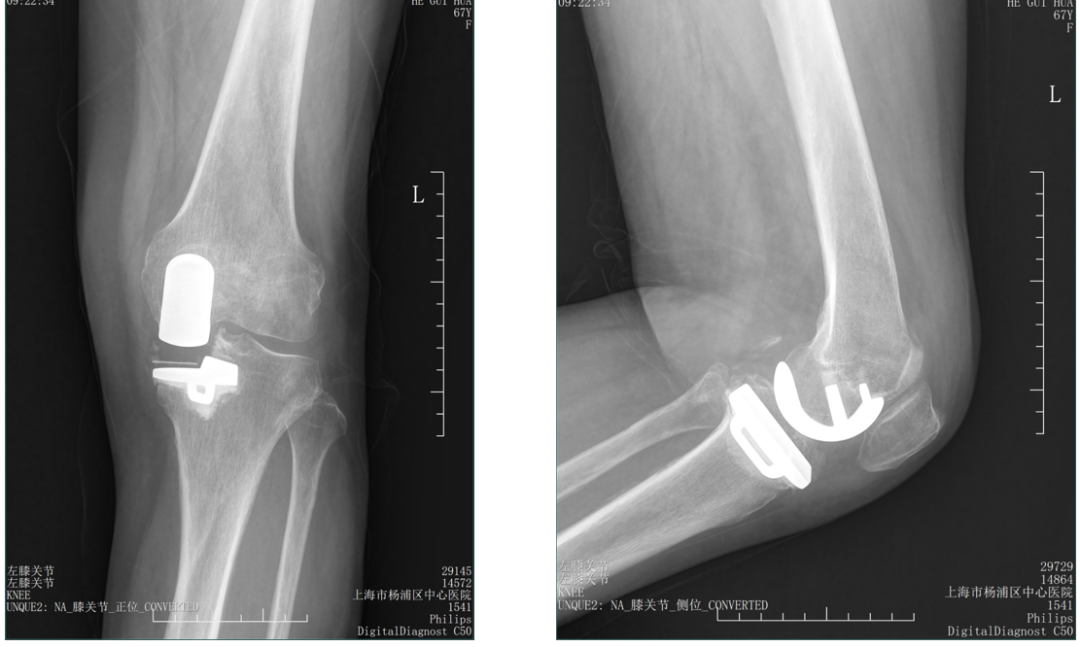

病例1

术后X-ray:正位片内旋,显示胫骨假体大小及位置佳(垂直截骨在棘突顶点、与内侧缘齐平、无内外翻)。

病例2

术后X-ray:标准正位片,显示胫骨假体大小及位置佳(垂直截骨在棘突顶点、与内侧缘齐平、无内外翻)。